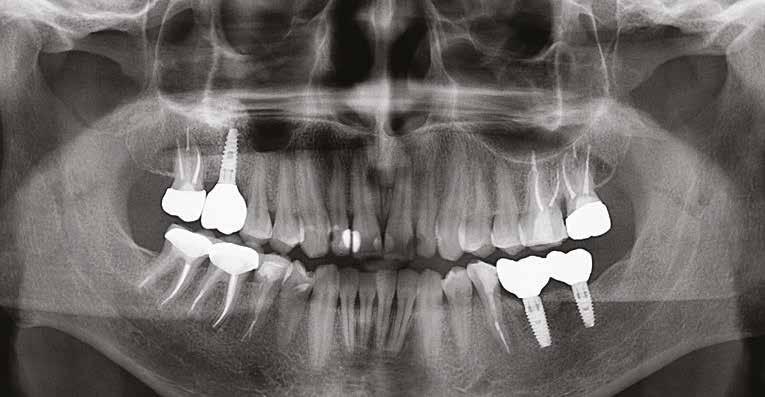

20–22. ábra: 2017-es, 2019-es és 2022-es panorámaröntgen-felvételek.

Egy 47 éves páciens jelentkezett nálunk egy alsó, hátsó foghiánnyal, ahol jelentős csontfelszívódást tapasztaltunk a moláris fogak korábbi eltávolítása miatt (1. ábra). Két implantátum körül is volt ínyrecesszió, illetve a keratinizált íny mennyisége minimális volt (kevesebb, mint 1 mm). 4 hónappal az implantációt követően ínykorrekciót végeztünk.

ságát egy ISO #15-ös endodonciai fájllal mértük 2 mm-re a marginális ínyszéltől meziálisan, disztálisan, illetve az implantátum tengelyében (mint referenciapont). A keratinizált íny szélességét parodontológiai szondával regisztráltuk a kiindulás és a kontrollvizsgálatok alatt. A méréseket elvégeztük a műtét előtt, közvetlenül utána, 4 héttel később, majd egy és két év elteltével. A klinikai paramétereket (keratinizált íny szélessége, lágyszövet volumen és recessziófedés) regisztráltunk a kiinduláskor és az utánkövetés időpontjai alatt. Kiinduláskor a feszes íny szélessége minimális volt (1 mm). A keratinizált ínyszélesség terén négy hétnél 2 mm-t sikerült nyerni, egy évnél 3 mm-t és öt év alatt 5 mm-t. A recessziót 100%-osan sikerült fedni 4 hét után, és ez nem változott sem egy év, sem öt év után.